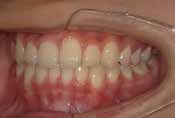

あごや骨格を正しく成長させる矯正治療

Aさん (矯正開始時:8歳)

Before

After

鼻がつまりやすく、口呼吸をしているために上あごが狭い状態でした。また上の前歯がかなり前へ傾いているため、お口をきちんと閉じていることができません。さらに、下の前歯もでこぼこしていました。

治療を終えて

装置によって上あごを拡大し、下あごを少し前へ成長させたことで、永久歯がきれいに並ぶスペースを確保しました。また、お口の機能が向上したことから鼻がよく通るようになり、口呼吸も改善され口も閉じやすくなったので顔の表情もよくなりました。

主訴・治療内容 下あごが後ろに下がり、出っ歯のようになっていることを心配して、無料相談に来院されました。

治療期間 2年半

費用 462,000円(税込)